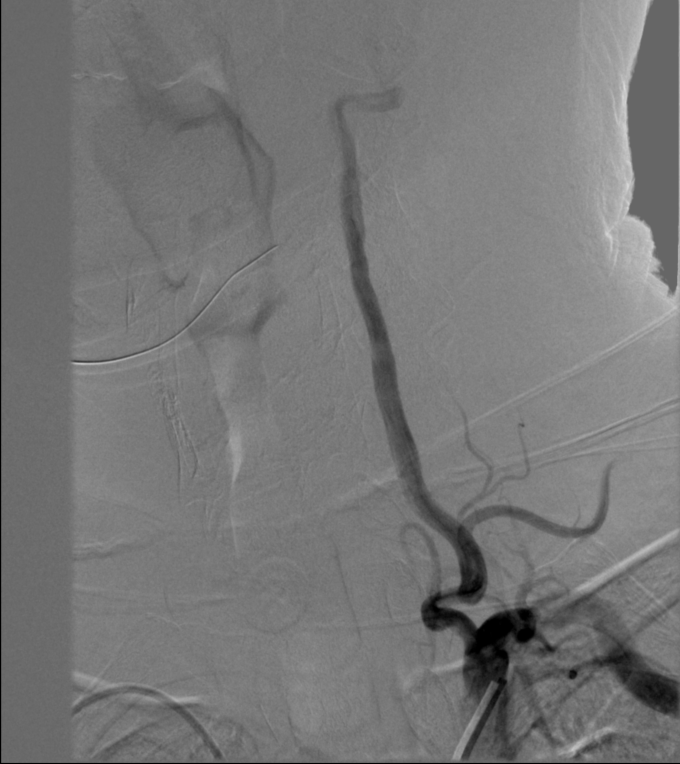

2022-10-11我院头颈DSA:

➤ 主动脉弓造影:Ⅰ型主动脉弓,右侧锁骨下动脉迂曲。

➤ 左侧颈内动脉造影:左侧颈内动脉C1段局限性狭窄约90%,C4-6段斑块形成,左侧大脑中动脉下干M2段狭窄约50%。